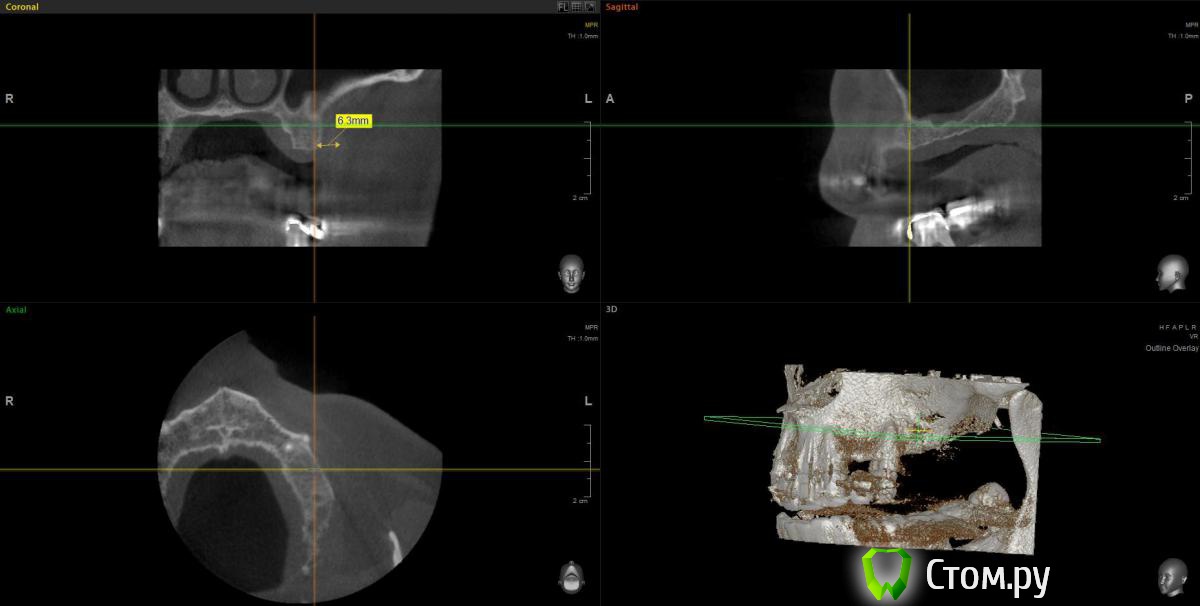

wladdX Опубликовано 11 февраля, 2014 Поделиться Опубликовано 11 февраля, 2014 (изменено) Прошу прощения за вторжение в чужую тему (администратор, поправьте), но ситуация похожа. Т.е. помимо синус-лифтинга надо увеличить ширину альвеолярного отростка. Предполагаю поступить примерно, как продемонстрировал Mane выше. Но может подойдёт "метод полужёстких каркасов? Кстати септа в пазухе замысловатая. По поводу остальных сегментов и прочих проблем - пациент на них не настроен, интересует его только зона 25,26,27 Изменено 11 февраля, 2014 пользователем wladdX Ссылка на комментарий